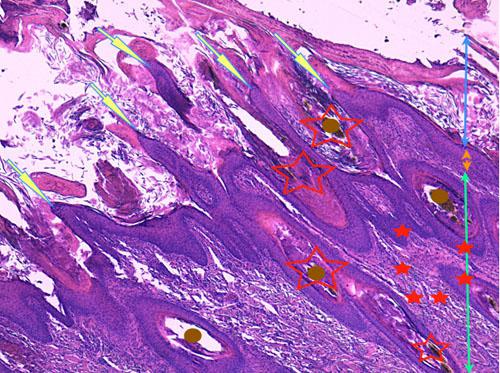

Photo 10 (Hémalun Eosine X 40) : l’épiderme et les infundibula folliculaires

sont hyperplasiques et hyperkératosiques. Des projections papillaires se forment aux marges des ostia folliculaires.

Le derme montre une inflammation péri-vasculaire.

Légendes de la Photo 10 :

- Double flèche bleue : couche cornée hyperkératosique

- Double flèche orange : épiderme (portion non kératinisée)

- Double flèche verte : derme

- Ronds marrons : tiges pilaires

- Flèches jaunes : projections papillaires de l’épiderme hyperplasique se formant aux marges des ostia folliculaires

- Étoiles rouges vides : follicules pileux, infundibula hyperkératosiques (orthokératose)

- Étoiles rouges pleins : infiltrat dermique périvasculaire